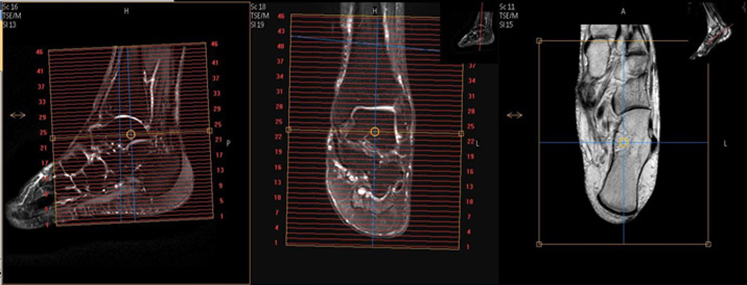

| AXIAL | T2 SPAIR | TSE | 4mm | 1mm | SPAIR | 15cm | Bottom of heel to above malleolus |

| SAG | T2 STIR | TSE | 3mm | 1mm | STIR | 15cm | Angle to Calcaneus |

| SAG | T1 | TSE | 3mm | 1mm | None | 15cm | Angle to Calcaneus |

| COR | T1 | TSE | 3mm | 1mm | None | 15cm | Include Tarsals |

| COR | T2 SPAIR | TSE | 3mm | 1mm | SPAIR | 15cm | Include Tarsals |